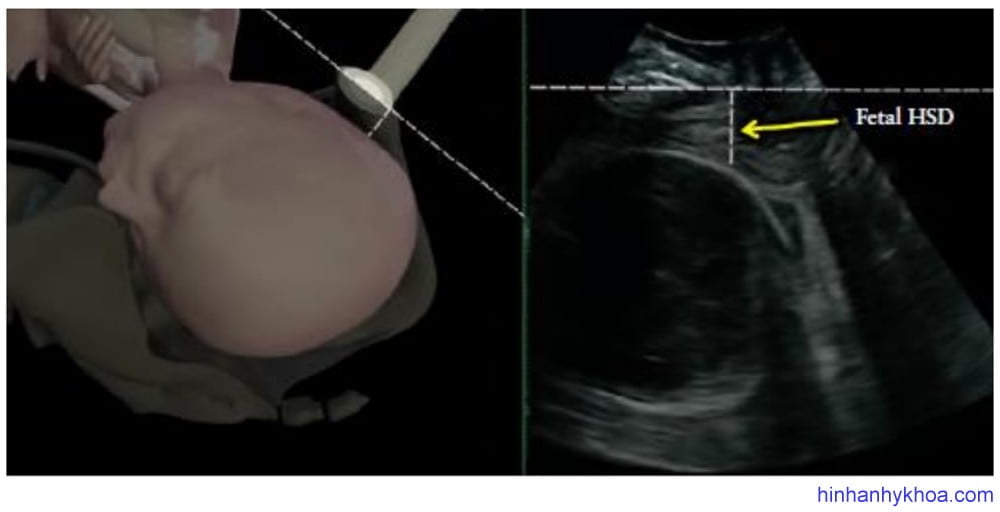

HSD là khoảng cách giữa phần thấp nhất của khớp mu sản phụ và đầu thai dọc theo đường dưới mu (Hình 10). Bởi vì khoảng trống có thể sờ thấy được giữa khớp mu và đầu thai được các nhà lâm sàng sử dụng rộng rãi trong đánh giá độ lọt, nên Youssef và cộng sự [51] đã đề xuất HSD như là dấu hiệu gián tiếp cho sự đi xuống của đầu thai. Trong một nghiên cứu đoàn hệ các trường hợp kiểu thế chẩm trước, việc đo đạc lặp lại thông số này cho thấy có mối tương quan nghịch tuyến tính với độ lọt thai, nghĩa là khi đầu càng xuống thấp thì trị số HSD càng ngắn lại (MỨC ĐỘ CHỨNG CỨ 2+). Hơn nữa, HSD còn cho thấy có mối tương quan thuận với HPD và tương quan nghịch với AoP32 (Hình 11). HSD chỉ có thể đo đạc được khi đầu thai xuống dưới đường dưới mu, tức độ lọt ≥ -3cm).

Hình 10: Vị trí đặt đầu dò và cách đo khoảng cách đầu – khớp mu (HSD) (Youssef và cs. [51])